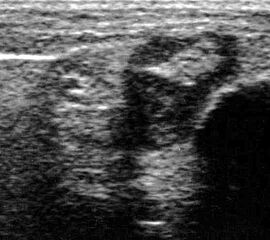

Durch Druck auf die ventrale Tibia läßt sich der Talusvorschub testen

Abbildung 20

Lagerung: Rückenlage, OSG in Plantarflexion, bei chronischer Instabilität auch Bauchlage.

Schnittebene: LS über Lig. talofibulare anterius und Lig. fibulocalcaneare.

Referenzstrukturen: Fibula und Talushals.

Befunde: Zunächst werden wie oben ausgeführt Lig. fibulotalare anterius und Lig. fibulocalcaneare im direkten Bandschnitt dargestellt. Dann erfolgt im Seitenvergleich die Stabilitätstestung unter Sicht auf den Monitor. Durch Druck von oben auf den Unterschenkel wird ein Vorschub des Fußes gegenüber der Tibia erzeugt, so dass, allerdings nicht in jedem Fall einer Banddurchtrennung, ein Vorschub des Talus gegenüber der Fibula (immer im Seitvergleich) am Monitor gemessen werden kann 3.